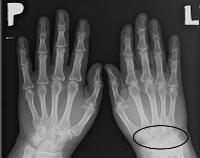

M24.6 Анкилоз сустава